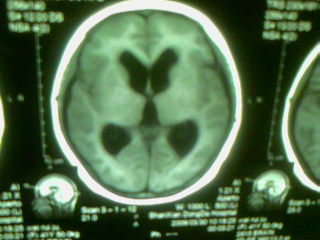

标题: MRI2125:女 45岁 头疼头晕3个月 [打印本页]

标题: MRI2125:女 45岁 头疼头晕3个月

手机照的,请各位谅解

1)考虑第四脑室脉络膜丛乳头状瘤,不排除室管膜瘤。2)阻塞性脑积水。

考虑 第四脑室室管膜瘤或脉络膜丛乳头状瘤伴梗阻性脑积水。

1)考虑第四脑室室管膜瘤,不排除脉络膜丛乳头状瘤。2)阻塞性脑积水。